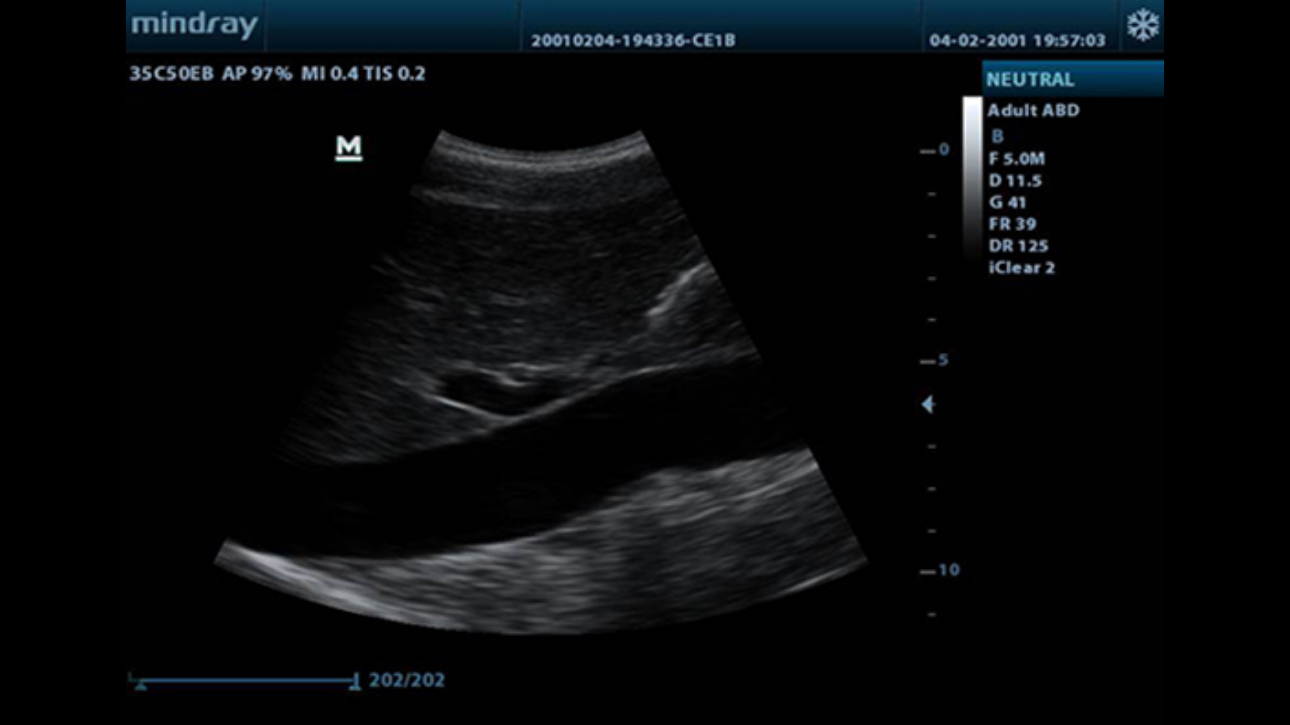

Tissue Harmonic Imaging

Utilizing second harmonics generated from tissue boundary layers, THI significantly enhances contrast resolution and improves image quality especially for technically difficult subjects.